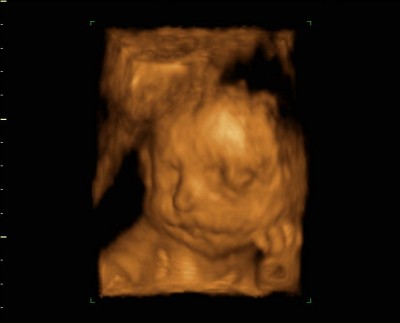

Dateianhänge

28+6 (2).jpg

28+6.jpg

der kleine 28ssw.jpg